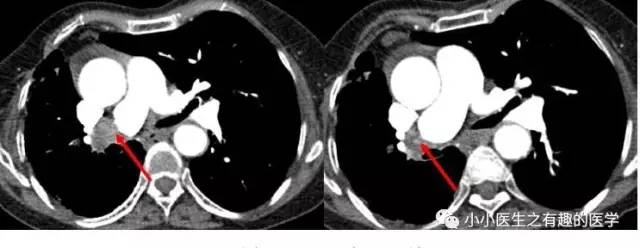

卫生部北京医院的病例。

亲们,这个胯子张的不是一般的大,可以去马戏团表演了,舞姿优美的一字马。大写的服。

亲们,这个左、右肺动脉主干几乎完全阻塞:一句话,蛋碎一地。也叫蛋碎肺栓塞,消失蛋肺栓塞,严重扯蛋肺栓塞。